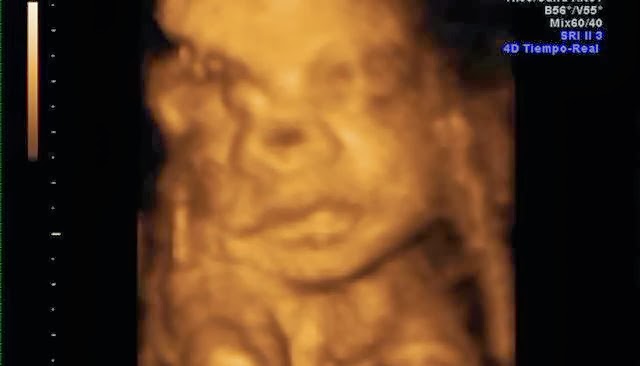

Su carita!Y estas son algunas capturas de pantalla de la eco 4d que me hice a principios de mes. Que ya de paso decir, que esta no me gustó NADA!! Tuvimos que esperar 2 horas para que nos cogieran, la eco nos la hicieron con prisas, y sólo se le vió la mitad de la cara.. así que para habernos gastado 100€ muy mal!! No os recomiendo la Ginecóloga de Gandia, Dra.Escrivá.

De momento parece que se parece a mami... jiji. Mi nariz, mi boca y mis mofletes :DEl padre se preguntó si era suyo.. jajaja, aunque tiene sus manazas.Y ahora os dejo unas fotitos de mi barriga en la playa, que aprovechando que esta semana aquí ha hecho muy buen tiempo nos hemos ido a hacernos un reportaje de fotos.